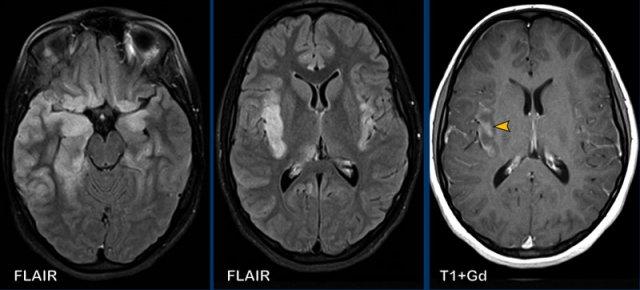

Các hình ảnh này của bệnh nhân nam 62 tuổi, nhập viện với các triệu chứng đau đầu, sốt và li bì.

Hình ảnh

Trên chuỗi xung FLAIR có tiêm thuốc tương phản từ, quan sát thấy lớp lót tăng tín hiệu dọc theo thành não thất bên trái, biểu hiện ngấm thuốc mỏng, rõ hơn so với hình ảnh trên chuỗi xung T1W có tiêm thuốc tương phản từ.

Trường hợp này được xác định là viêm màng não do Lyme, có biến chứng viêm não thất.

Tiếp tục xem thêm một số hình ảnh bổ sung…

Có hạn chế khuếch tán trong não thất bên trái.

Ngấm thuốc màng não mềm được ghi nhận rõ trên chuỗi xung FLAIR có tiêm thuốc tương phản từ (đầu mũi tên).

Dấu hiệu này không đặc hiệu cho viêm màng não do Lyme; các nguyên nhân nhiễm trùng khác cũng cần được đưa vào chẩn đoán phân biệt.

Khi có ngấm thuốc dây thần kinh mặt hai bên, cần luôn nghĩ đến viêm màng não do Lyme.

Các hình ảnh này của bệnh nhân có áp xe vùng đỉnh.

Áp xe biểu hiện hạn chế khuếch tán trung tâm với thành ngấm thuốc tương đối dày.

Đầu mũi tên màu vàng chỉ vào lớp ngấm thuốc mỏng của thành não thất.

Kết luận

Áp xe lan vào trong não thất, dẫn đến viêm não thất.

Các hình ảnh này của bệnh nhân nam 63 tuổi, có áp xe não nhỏ (mũi tên vàng) tại trung tâm bán bầu dục bên phải.

Lưu ý có sự xâm lấn não thất đáng kể.

Bên cạnh ngấm thuốc thành não thất, còn ghi nhận hạn chế khuếch tán trong áp xe và trong lòng não thất (đầu mũi tên).